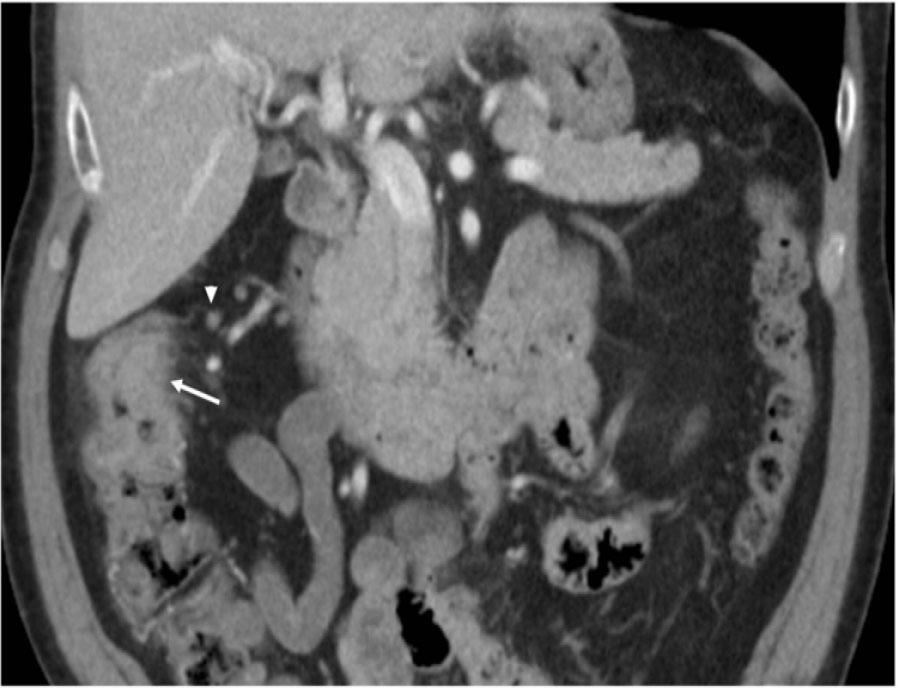

Figure 1: